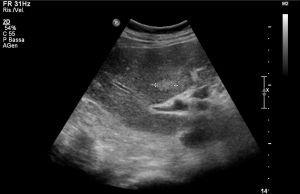

Ad oggi sono state identificate con l’ecografia addominale prevista dal protocollo, 9 neoplasie del parenchima epatico: 5 angiosarcomi (Fig. 1-4) (di cui 2 viventi) e 4 epatocarcinomi (Fig. 5-7) (di cui 1 vivente), successivamente sottoposte a studio TC e tutte confermate dalla diagnosi istologica.

Fig.4. Caso 2 di angiosarcoma epatico

Fig.5. Caso di HCC